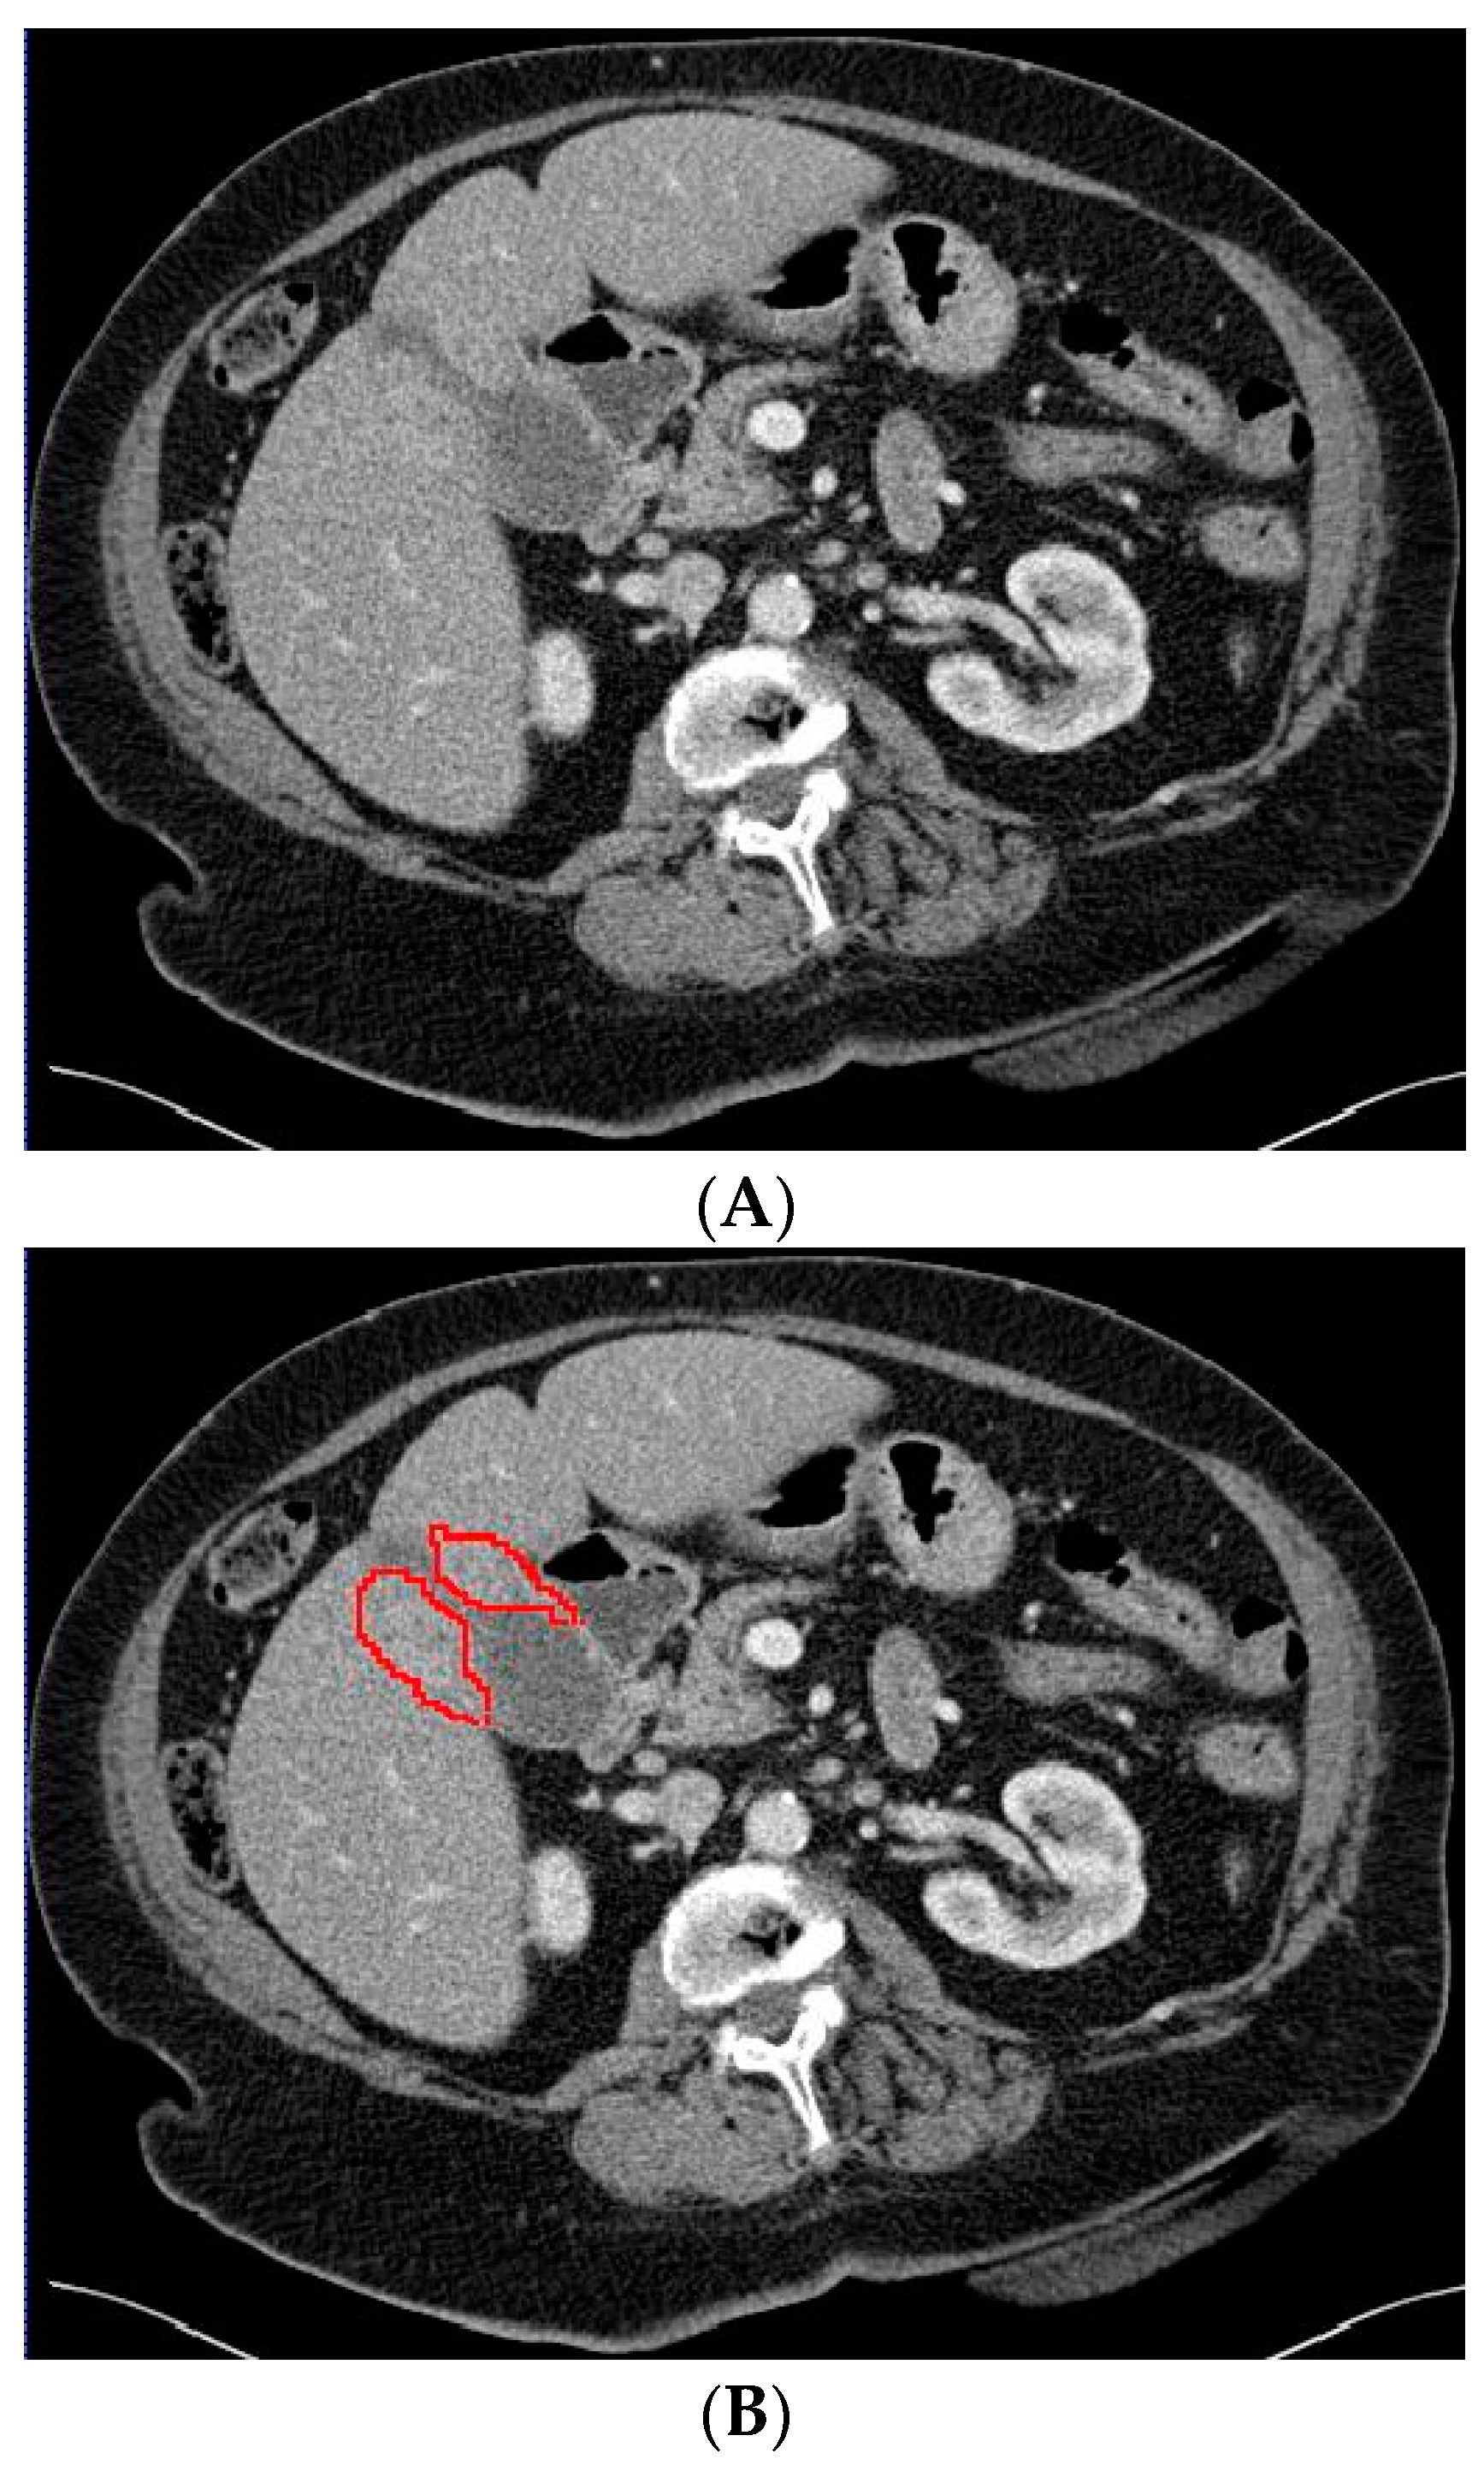

2.3. Deep Learning Model Based on Gallbladder and Liver Parenchyma

In a previous study, the suspicion of invasion of adjacent liver parenchyma was observed to be positively related to GBC [5]. Therefore, in addition to using only the gallbladder on CT images when training the deep learning model, a separate analysis was performed to investigate whether the combination of the gallbladder and adjacent liver parenchyma could increase the performance of the deep learning model when differentiating between GBC and benign gallbladder disease. The segmentation of a 2 cm rim of liver parenchyma adjacent to the gallbladder was automatically generated and adjusted by an experienced abdominal radiologist if necessary. The adjacent liver parenchyma was combined with the segmented gallbladder as training data for the deep learning model. Figure 4 shows examples of input CT images with segmentation of both the gallbladder and 2 cm of adjacent liver parenchyma. The deep learning model based on the combination of the gallbladder and adjacent liver parenchyma was trained and tested by the same methodology as described for the model solely based on the gallbladder.